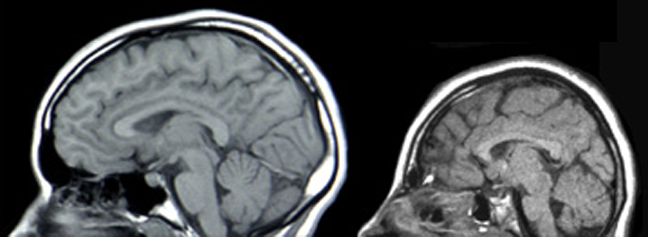

Fotografie + Description: MRIs of a normal individual (left) and a patient with microcephaly caused by an ASPM mutation (right).

- Date: Published: March 23, 2004

- Source: (2004) Evolutionary History of a Gene Controlling Brain Size. PLoS Biol 2(5): e134. doi:10.1371/journal.pbio.0020134